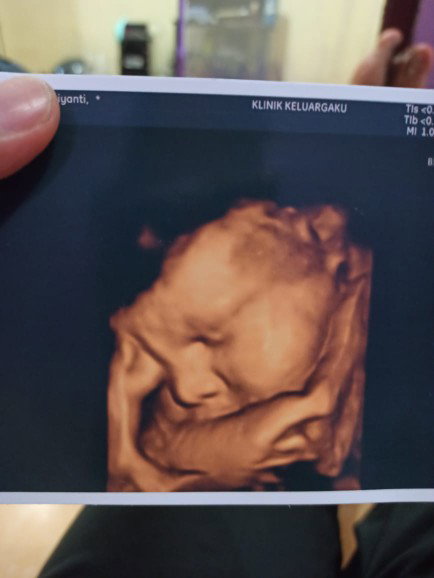

BISMILAHIRRAHMANIRAHIM, MINTA KEIKLASAN DOA NYA BUNDA SUPAYA DEDEK LAHIR SEBELUM HPL, DIBERI KESEHATAN JASMANI ROHANI DAN DI MUDAHKAN SEGALA PERSALINAN NYA, UNTUK BUNDA YANG MENGAMINKAN SEMOGA SELALU DIBERI KEBAHAGIAAN SERTA DIPERMUDAHKAN SEGALA URUSAN NY

🤲🤲🤲 terima kasih bunda atas segala doa nya...